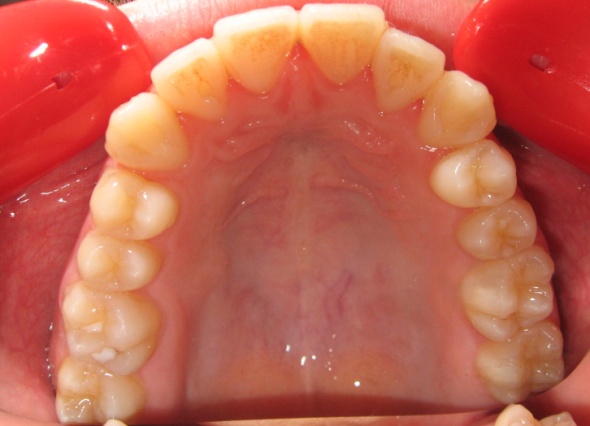

2 - Appareillage utilisé : expansion palatine et multiattaches

Cette étape montre l’utilisation d’un disjoncteur palatin pour élargir le maxillaire. Contrairement à la mandibule, le palais présente une suture médiane, véritable joint de croissance, que l’on peut activer chez l’enfant ou l’adolescent. En écartant progressivement les deux moitiés du maxillaire, on crée un gain d’espace réel, non dentaire. Cela permet de rétablir une largeur d’arcade suffisante, sans extraction, en amont de l’alignement multiattaches.